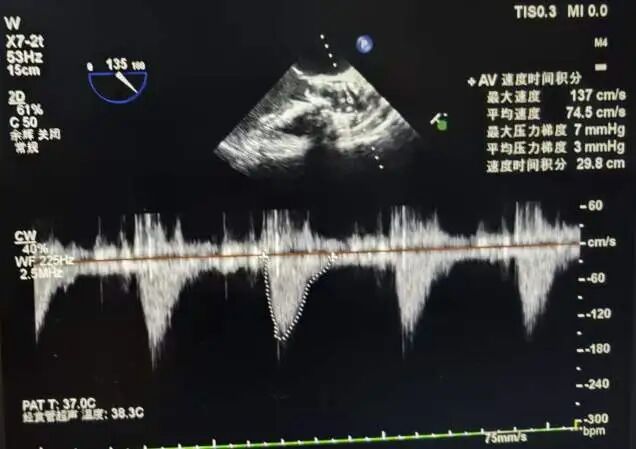

术前超声所见与诊断

主动脉瓣增厚钙化、开放受限,确诊主动脉瓣钙化并狭窄(重度)并反流(轻度);主动脉瓣上血流速度436cm/s,MPG:42mmHg,PPG:76mmHg,AVA:1.1cm²

术后即刻超声评估

14.jpg

人工生物瓣在位,瓣架固定牢固,瓣叶活动良好,瓣膜功能正常。